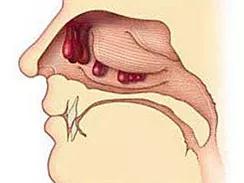

鼻息肉,顾名思义,就是在鼻腔粘膜的表面长的一个增生组织团,所以常见的表现为鼻子阻塞,和鼻内的分泌物增多,还伴有面部疼痛,产生肿胀感,还有可能导致嗅觉的减退或消失。鼻息肉是鼻部常见的疾病,大多数发生在成年人的身上。

常见的鼻息肉症状表现在持续性鼻塞,同时随着鼻息肉的长大而加重,鼻腔内分泌物增加,还经常会答喷嚏,严重的还会引发鼻窦感染,发炎化脓。鼻塞严重的患者说话时也会带着鼻音,睡觉时还容易打呼。鼻息肉很大的时候,打呼的时候还能感觉到鼻腔内有东西随着呼吸移动。

有时体积很大,甚至达数厘米大小充塞鼻腔而造成鼻塞、呼吸不通畅,或呈活瓣样启闭。